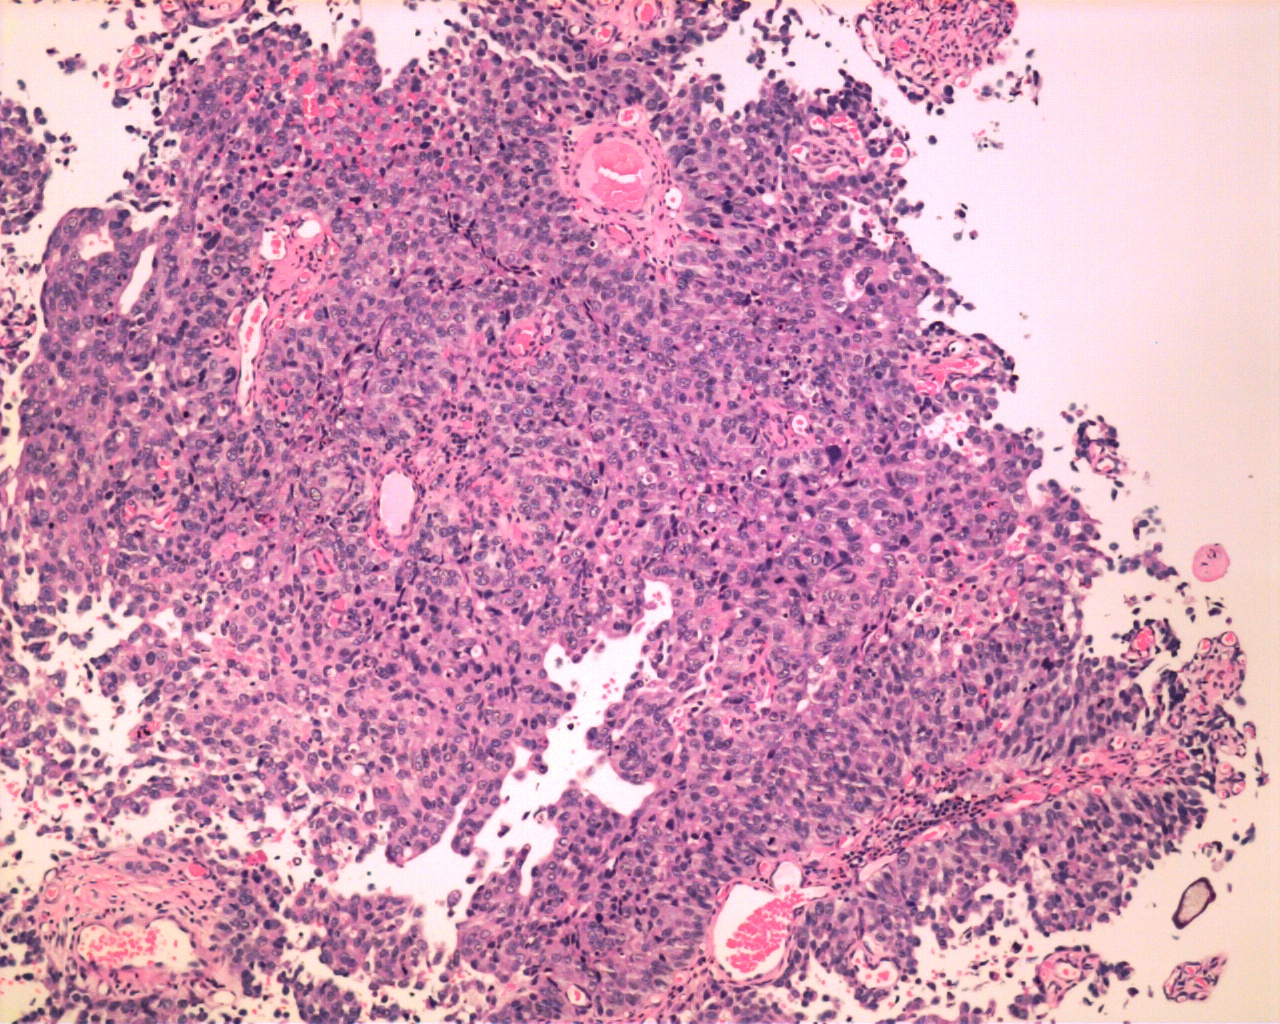

Consensus grade: High-grade papillary urothelial carcinoma (HG-PUC)

Case description (by case creator):